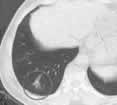

2001-2003年,冈山济生会医院对80例肺肿瘤患者进行了RFA治疗,其中包括了218个病变部位。首次RFA后,30例(104个病变部位)生存超过1年以上(男性19例,女性11例,平均年龄64岁);原发病灶为直肠癌4例,肾癌5例,肺癌5例,肝癌2例。104个病变部位的肿瘤直径为3~55 mm(平均18.9 mm),约半数在30 mm以下。在12~28个月(平均18个月)的观察期间,定期行CT检查,必要时追加RFA治疗。肾癌肺转移1例(3个病灶)、食道癌肺转移1例(1个病灶)经RFA治疗6~7个月后被切除,到目前已随访了12~15个月,未见肿瘤的局部复发和肺转移(图)。

图2.

70岁男性肺腺

癌患者的手术后肺转移灶

图3.

经2次RFA治疗后,

原病变部位成为瘢痕。